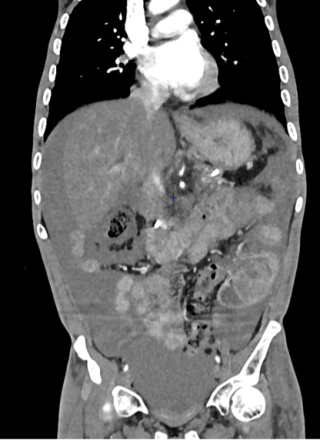

A 37-year-old man with an history of cirrhosis and atrial fibrillation treated with apixaban was admitted for weakness and dizziness. On admission, he was hypotensive and tachycardic, with signs of peripheral hypoperfusion and diffuse abdominal tenderness. Laboratory investigations revealed severe anemia (Hb 46 g/L), marked coagulopathy, and metabolic acidosis with elevated lactate levels. Abdominal CT scan demonstrated a left flank mesenteric lesion exerting mass effect on adjacent small bowel loops, associated with a large-volume acute hemoperitoneum. Emergency exploratory laparotomy revealed approximately 4 liters of hemoperitoneum and a large jejunal intramural hematoma with complete serosal rupture. Segmental jejunal resection was performed with temporary abdominal closure. A planned second-look laparotomy allowed jejunojejunal anastomosis. Histopathological examination confirmed a submucosal hematoma with preserved mucosa and no evidence of ischemia.